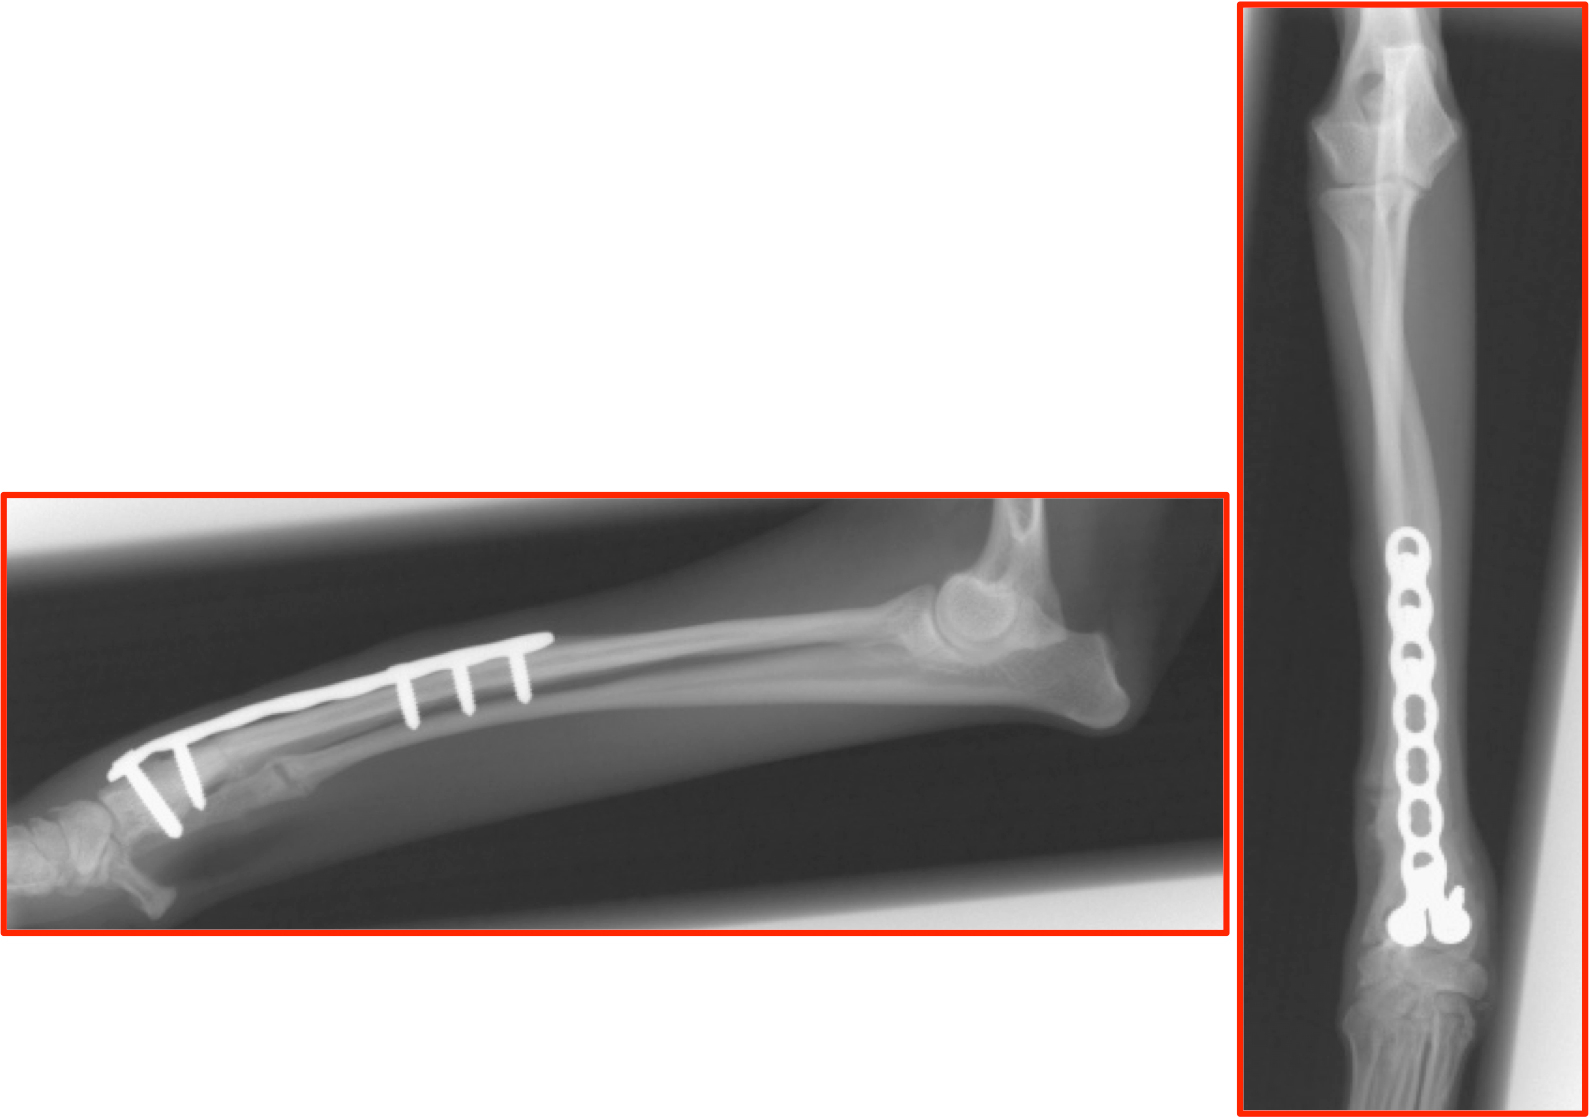

<本手術>

・実骨切り時には模擬手術で使用した3Dプリンターモデルで骨切り線を確認しながら実施。

・模擬手術にて形状設定したプレートを使用しプレートに合わせ骨切り部の固定実施。(模型もインプラントも手術時には滅菌済)

・手術時間は切皮よりプレート固定まで40分(消毒・縫合時間を除く)

・骨切り部の良好な癒合所見。インプラントに異常は認められない。

術後8週間後 画像

http://www.atpress.ne.jp/releases/54567/img_54567_8.jpg